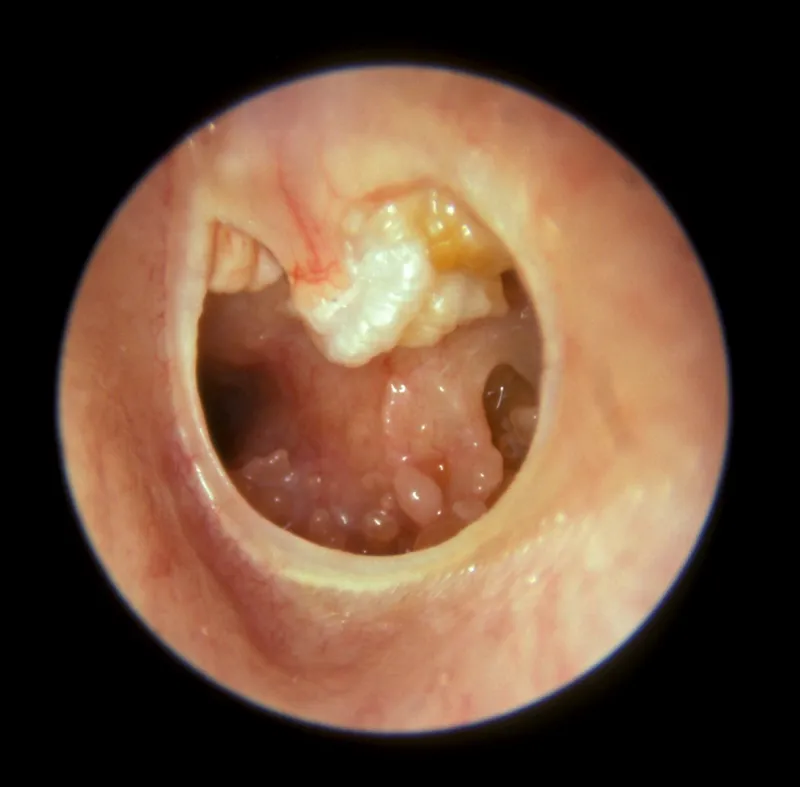

- Signs (Otoscopy):

- Attic or posterosuperior marginal perforation or deep retraction pocket.

- Visible whitish/pearly keratin debris or flakes.

- Ossicular chain erosion, granulation tissue, or aural polyp.

- Otoscopy: Key initial exam. Reveals attic or posterosuperior pars tensa retraction pocket, keratin debris, granulations, or polyp.